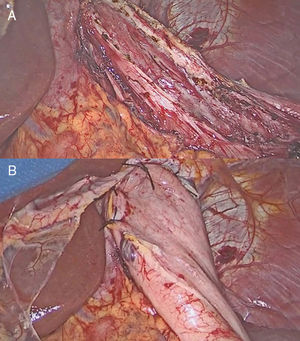

A 68-year-old man was evaluated in our clinic for intermittent dysphagia, regurgitation of liquids and solids, and chest pain. Esophagogastroduodenoscopy revealed a slightly dilated esophagus with retained food. Barium swallow showed esophageal indentations, with the characteristic “corkscrew” appearance (Fig. 1 arrows). High-resolution manometry confirmed the diagnosis of diffuse esophageal spasm (DES), with a hypertensive and non-relaxing lower esophageal sphincter. The ambulatory pH monitoring was normal. Because of the patient's progressive symptoms, which did not respond to calcium channel blocking agents and pneumatic dilatation, we performed a long laparoscopic Heller myotomy with Dor fundoplication (Fig. 2). Postoperative course was uneventful, and the patient was discharged after 24h on a soft diet. DES is a rare primary esophageal motility disorder characterized by dysphagia and intermittent chest pain. In these patients, the surgical myotomy should be extended more proximally than in patients with achalasia to obtain better relief of symptoms.